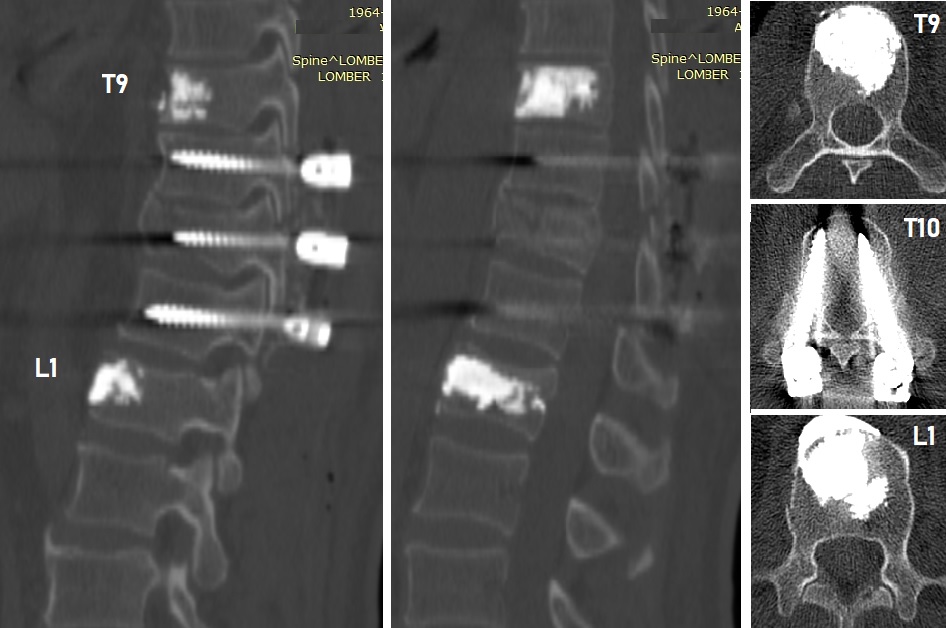

AMELİYAT

Hastaya T9 ve L1 vertebralarına kifoplasti

(6'şar ml metilmetakrilat) ve T10-11-12 vertebralarına transpediküler

stabilizasyon uygulandı. Laminalar ve fasetler üzeri kısmi dekortike

edilerek füzyon artırıcı (Ca-fosfat granül) materyal ve alandan alınan

otojen kemikler serildi. T11 laminası ve faset ekleminin iki yanlı

kırık olduğu görüldü. Laminektomi yapılmadı.